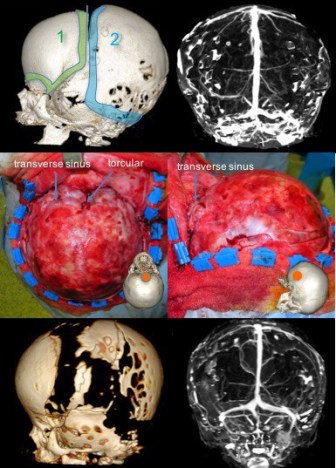

la craniotomie expose les sinus veineux, permettant une bonne décompression veineuse.

- taille d’un volet pariéto-occipital rasant le sinus latéral

![]()

- attention à l’adhérence de la suture restée perméable au sinus sigmoïde

- volet retourné à 180°

- barrel-staves du côté synostotique pour corriger le bombement antérieur et rediriger vers l’arrière la poussée cérébrale.